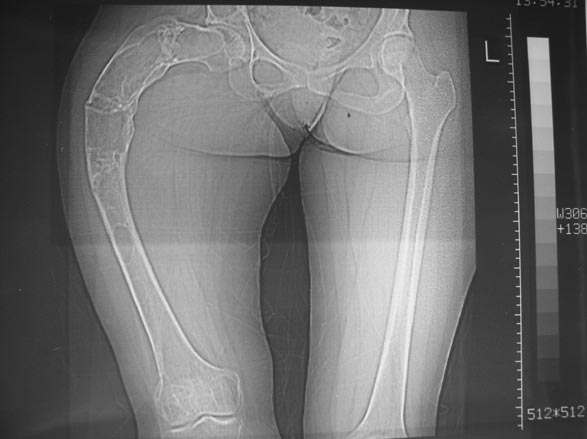

Уважаемые коллеги! С Новым годом и самых светлых пожеланий!В ноябре этого года я обращался с просьбой о помощи в выборе тактики лечения больной с деформацией бедра на почве фиброзной дисплазии. Были получены интересные и очень полезные советы по операции.

Хотелось бы показать, что получилось в результате.Операция выполнялась с помощью А.Н.Челнокова. Очень понравилась технология выполнения блокируемого остеосинтеза с использованием спицевого дистрактора, модифицированный гвоздь с латерализованным проксимальным отделом и возможностью многовинтовой фиксации проксимального и дистального участков бедра.

Прекрасная работа, поздравляю Александра и Леонида с удачной реконструкцией: длины и контура бедра.